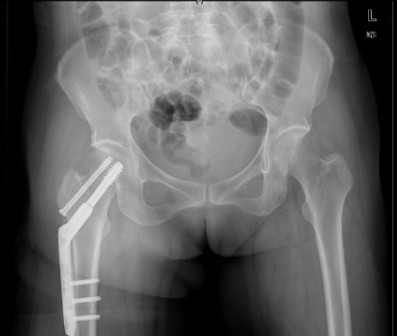

患者女,61岁,因“摔伤致右髋关节疼痛、活动受限9小时”入院。患者于入院前9小时行走时不慎摔倒,右侧肢体着地,当即感右髋关节及右大腿上段疼痛,活动受限,不能自行站立,受伤时及伤后无昏迷,无恶心、呕吐,无心累、气促,无腰痛及肉眼血尿。因休息后无缓解,急诊到当地医院行骨盆平片提示“右股骨颈骨折”,未做任何治疗,患者为求进一步治疗,遂急诊来我院,急诊以“右股骨颈骨折”收入住院。

诊断:1、右股骨颈骨折(Garden III);2、骨质疏松症 治疗:择期手术